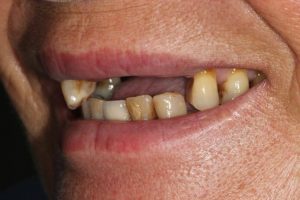

This patient had broken their upper front tooth and the exisitng dental crown had fallen off. The underlying root was unfortunatley irreparable.

The dental root was subsequently removed and an implant placed at the same time. The implant had a temporary crown placedon the same day.

The ‘After’ photos shows the final crown that was made after 3 months. The implant crown was made to match the form and colour of the exisiting teeth to give an overall natural aesthetic finish.